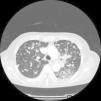

Presentamos el caso clínico de una mujer de 63 años no fumadora, de origen japonés, que consultó por tos seca de varios meses de evolución. El estudio con scanner TAC, tomografía por emisión de positrones (PET/TAC) y fibrobroncoscopia fue concluyente con adenocarcinoma de pulmón TTF1 positivo en estadio diseminado (masa pulmonar en lóbulo inferior izquierdo con múltiples nódulos bilaterales y lesiones óseas). Debido a las características de la paciente se solicitó el estatus mutacional del receptor del factor de crecimiento epidérmico (EGFR), confirmándose delección del exón 19 y optándose por iniciar primera línea con anti-EGFR. La tolerancia fue excelente, con mejoría clínica importante y el TAC de reevaluación mostró una mejoría evidente de las lesiones cumpliendo por criterios RECIST datos de respuesta parcial. Sin embargo, 2 meses después la paciente comenzó con dolor importante a nivel torácico izquierdo y sensación disneica. Se optó por adelantar el TAC de control, observándose importante progresión a nivel pulmonar y óseo, con aumento significativo del tamaño y número de los nódulos pulmonares y aparición de una lesión costal con masa de partes blandas asociada (fig. 1). En esta situación, ante la rápida progresión de la enfermedad en una paciente con cáncer de pulmón EGFR mutado, se optó por rebiopsiar para tipificar de nuevo el tumor. El resultado fue compatible con adenocarcinoma de pulmón EGFR mutado, identificándose 2 mutaciones distintas: por un lado, la mutación del exón 19 conocida y, por otro, la mutación T790M del exón 20, que confiere resistencia a los anti-EGFR. Debido a lo anterior se decidió suspender el inhibidor e iniciar quimioterapia. Sin embargo, el estado general de la paciente empeoró en pocos días, falleciendo poco tiempo después.